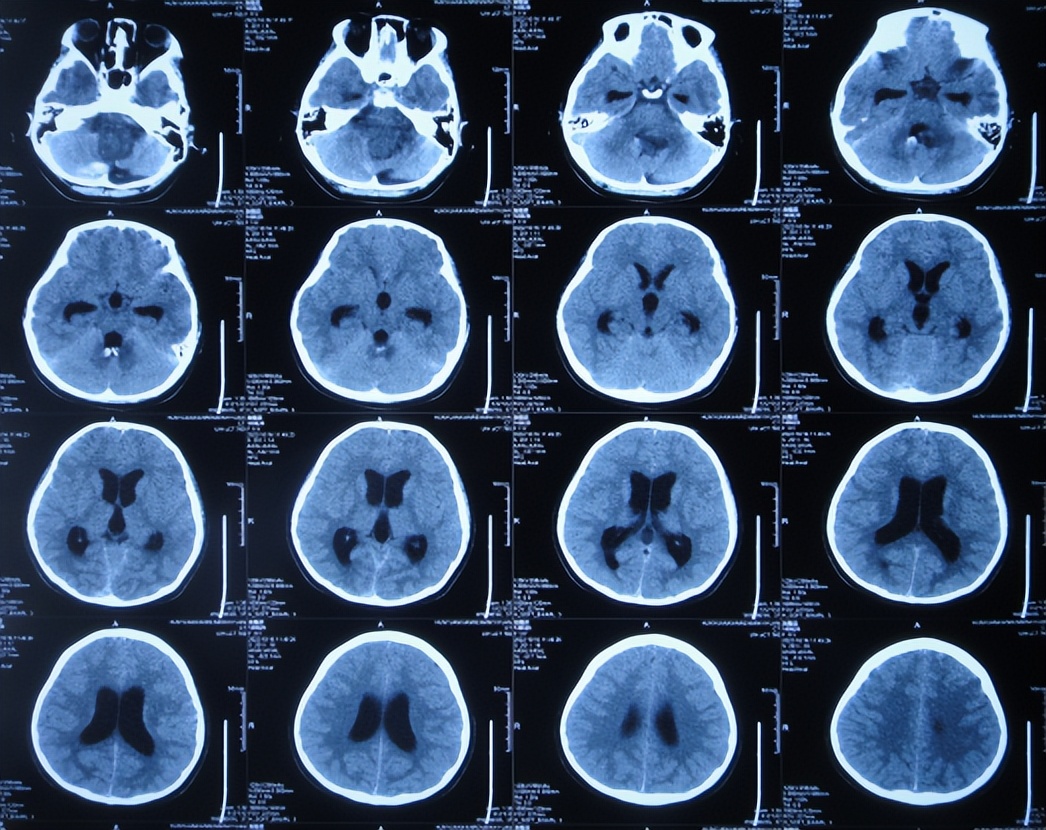

患儿于2022年10月10日,无诱因出现颈部疼痛,伴恶心呕吐、精神差,当时意识清楚,没有就诊,5天后即2022年10月16日,凌晨再次出现恶心呕吐多次,精神差,变得嗜睡,能被叫醒,就诊于山西省大同市浑源县某医院,查颅脑CT( 图-1 )示“小脑出血”,给予止血对症治疗。

图-1: 2022年10月16日颅脑CT上午11点